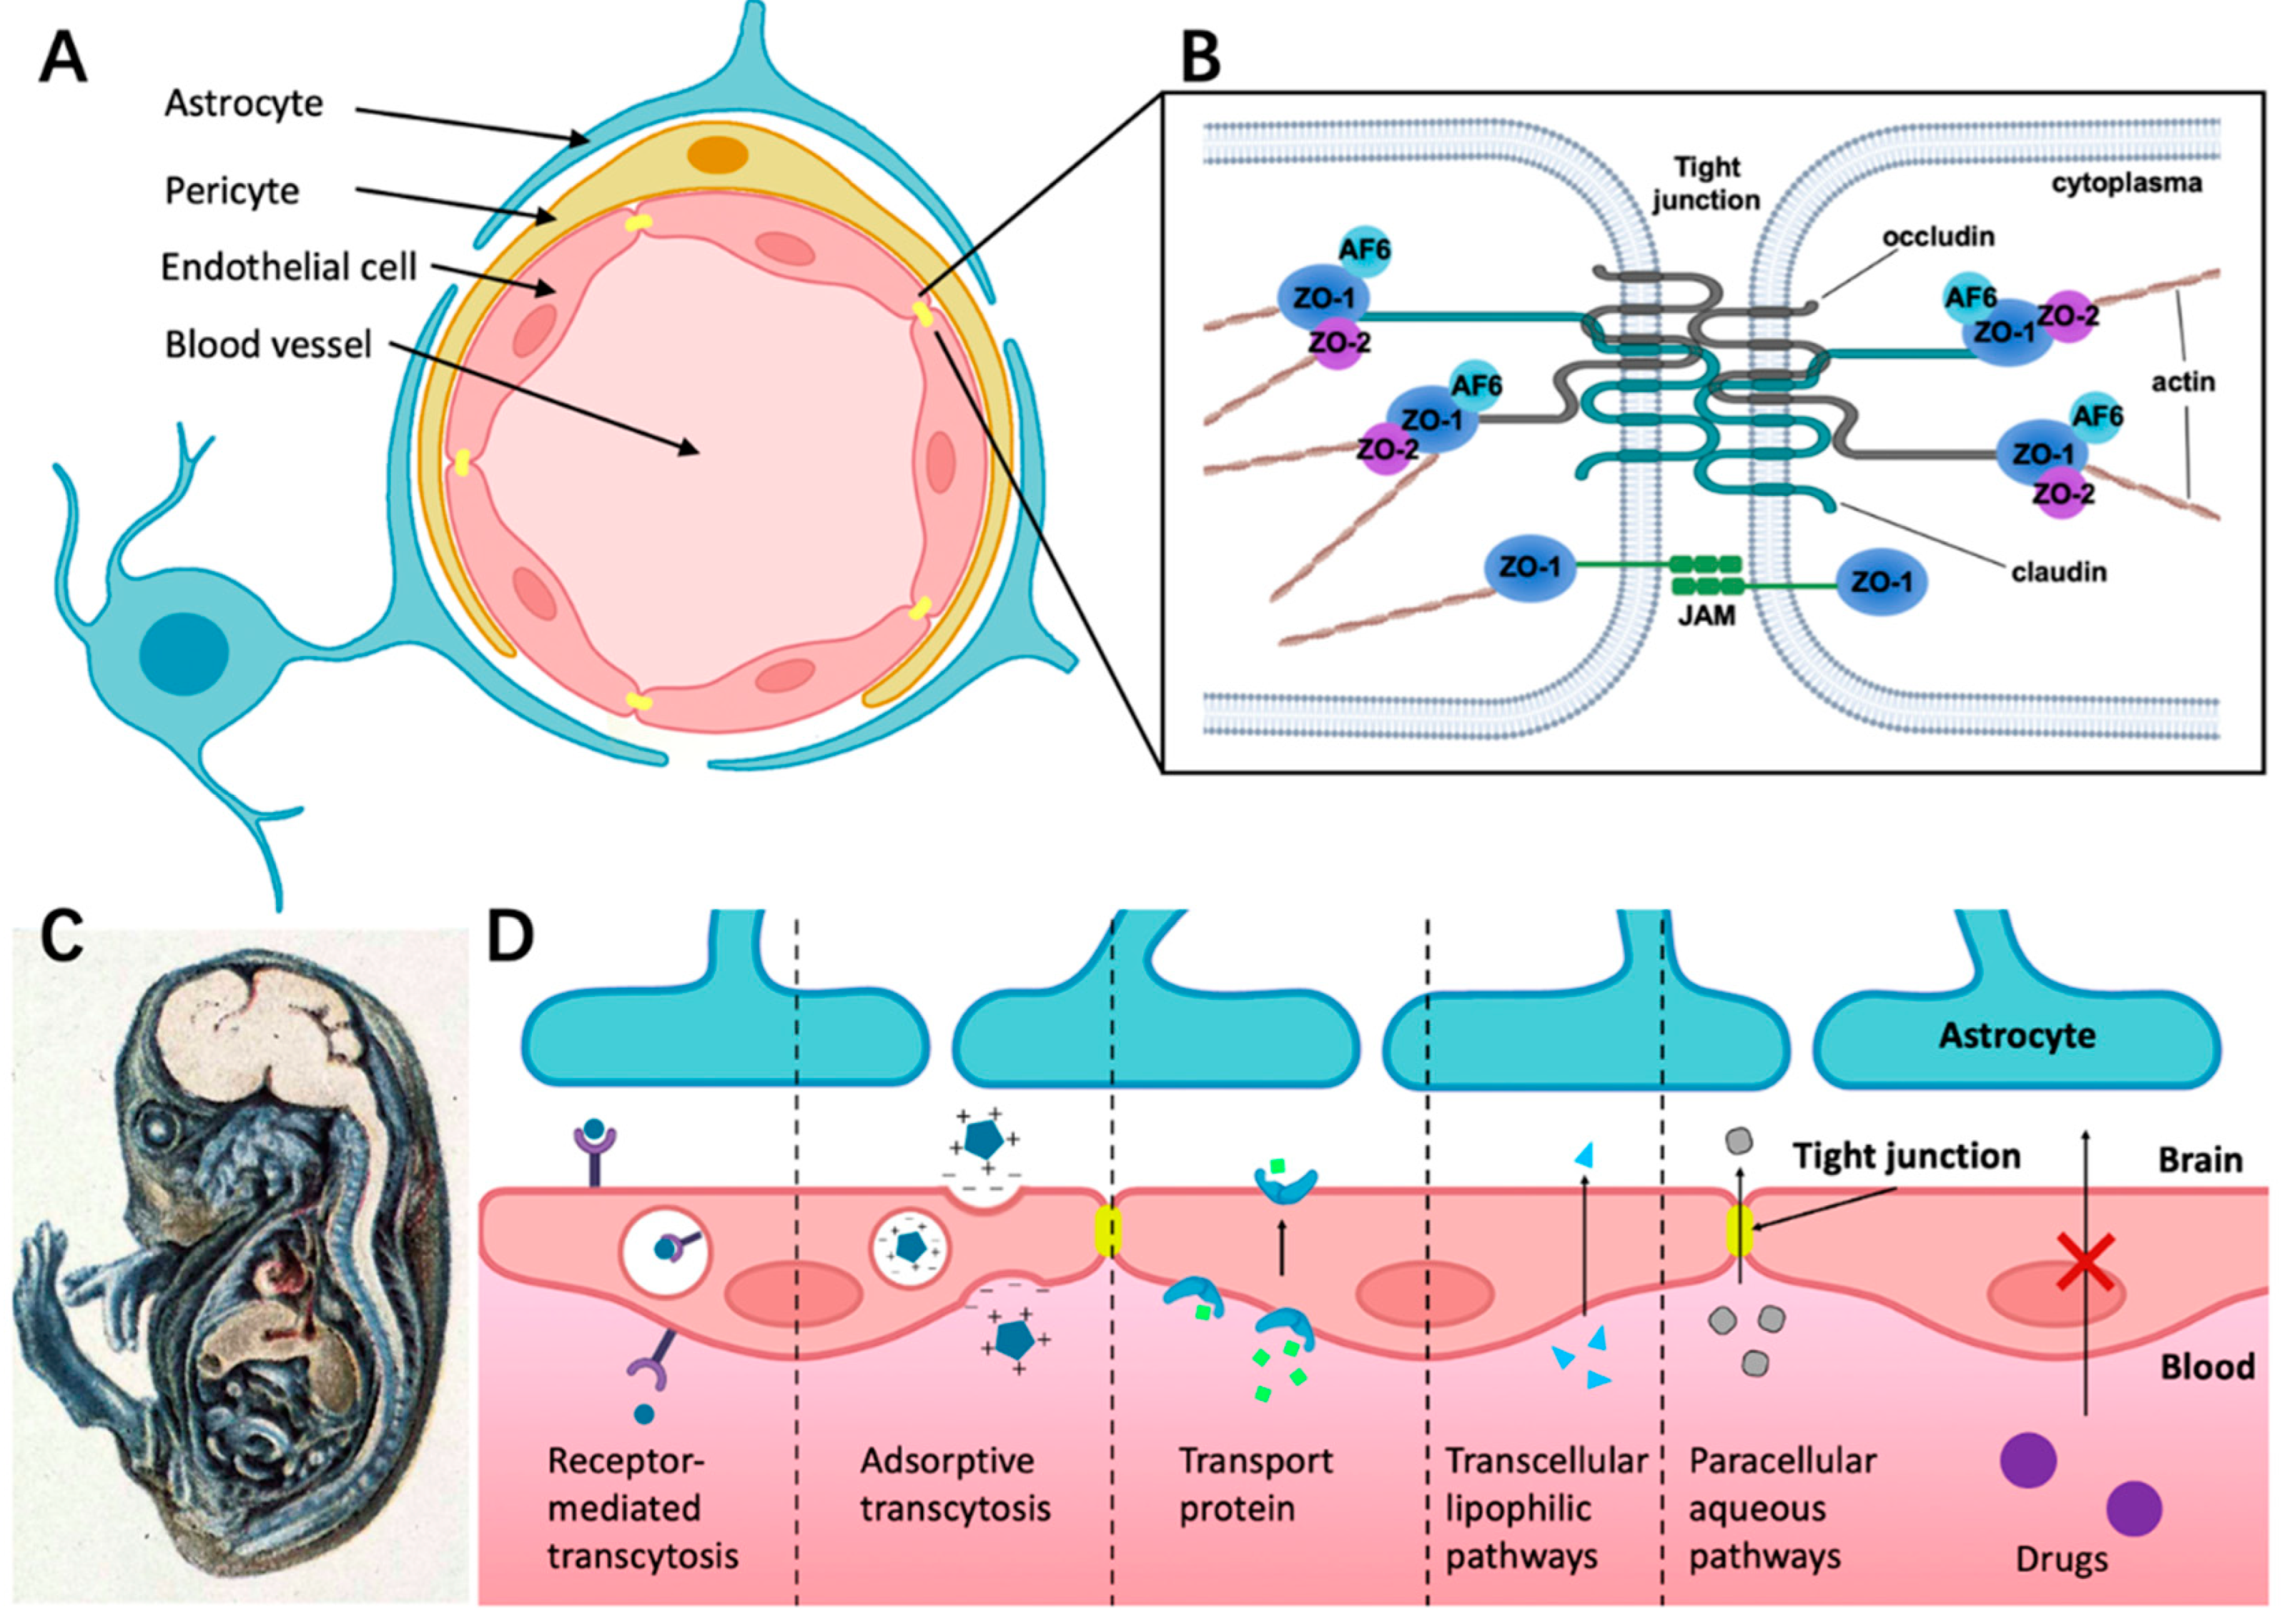

2. Structure of BBB and Substance Transportation

2.1. Cellular Structure of BBB

2.2. Structure Foundation of Tight Junctions (TJs)

2.3. Different Ways for Substances Crossing the BBB under Physiological Conditions